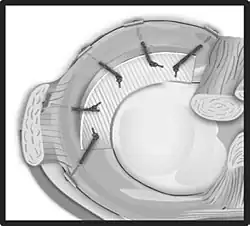

Korbhenkelriss

Ein Korbhenkelriss ist die Bezeichnung für einen parallel zu der Hauptrichtung der Fasern verlaufenden Meniskusriss. Der Meniskus wird dabei entlang seines Verlaufes längs gespalten, das vordere und das hintere Ende des Fragmentes behalten weiterhin Verbindung zum Rest des Meniskus. Der freie Rand disloziert in den Gelenkspalt und verursacht akute Schmerzen sowie vor allem eine Blockade, die eine volle Streckung des Kniegelenks nicht erlaubt.

Bei einer Meniskusnaht wird der Riss mit speziellem Nahtmaterial, Nahtsystemen oder Meniskuspfeilen aus resorbierbaren Materialien wieder befestigt. Dies ist allerdings nur bei bestimmten Rissenformen und in durchbluteten Bereichen (rot-rote bzw. rot-weiße Zone) möglich.[5] Bei jüngeren Patienten wird auch bei weniger basisnahen Rissen eine Refixation versucht, um denkbare Folgen einer Meniskusresektion auf das Gelenk möglichst zu vermeiden. Je früher Meniskusrisse operativ versorgt werden, desto größer ist die Aussicht auf eine Ausheilung.[6] Zur Verbesserung der Einheilung wird neben den Nähten eine Anfrischung der Risszone (sogenanntes Needling, also „Nadeln“) durchgeführt, wodurch die Durchblutung lokal verbessert wird. Bei ausgedehnten Rissen mit hoher Bedeutung einer Ausheilung wird zusätzlich die Eröffnung der Spongiosa im Kniegelenk durchgeführt. Dazu wird mit einer arthroskopischen Ahle oberhalb der Notch zwischen den Kondylen eröffnet. Das dadurch austretende stammzellreiche Blut trägt erheblich zur Heilung bei. Das erklärt auch, warum Meniskusnähte aufgrund der Anlage von Bohrkanälen bei einer Kreuzbandplastik eine deutliche besser Heilungstendenz haben. Anschließend muss der genähte Meniskus heilen. Dazu wird die Bewegung des Kniegelenks in der ersten Phase nach der Operation eingeschränkt, wozu eine Schiene zur Bewegungslimitierung getragen wird. Die Belastung kann schnell aufgebaut werden, da der Meniskus dabei nicht belastet wird. Nach etwa drei Wochen kann die Bewegung des Kniegelenks zunehmend freigegeben werden, eine vollständige Aufnahme der sportlichen Tätigkeit erst nach einem halben Jahr, bei gutem Verlauf der Heilung eventuell auch früher. „Sanfte“ sportliche Tätigkeiten, wie zum Beispiel Krafttraining, Radfahren oder Schwimmen können nach circa zwei Monaten aufgenommen werden. Ein Erhalt des Meniskus mittels Naht ist die erfolgreichste Behandlung mit der besten Perspektive für das Kniegelenk.